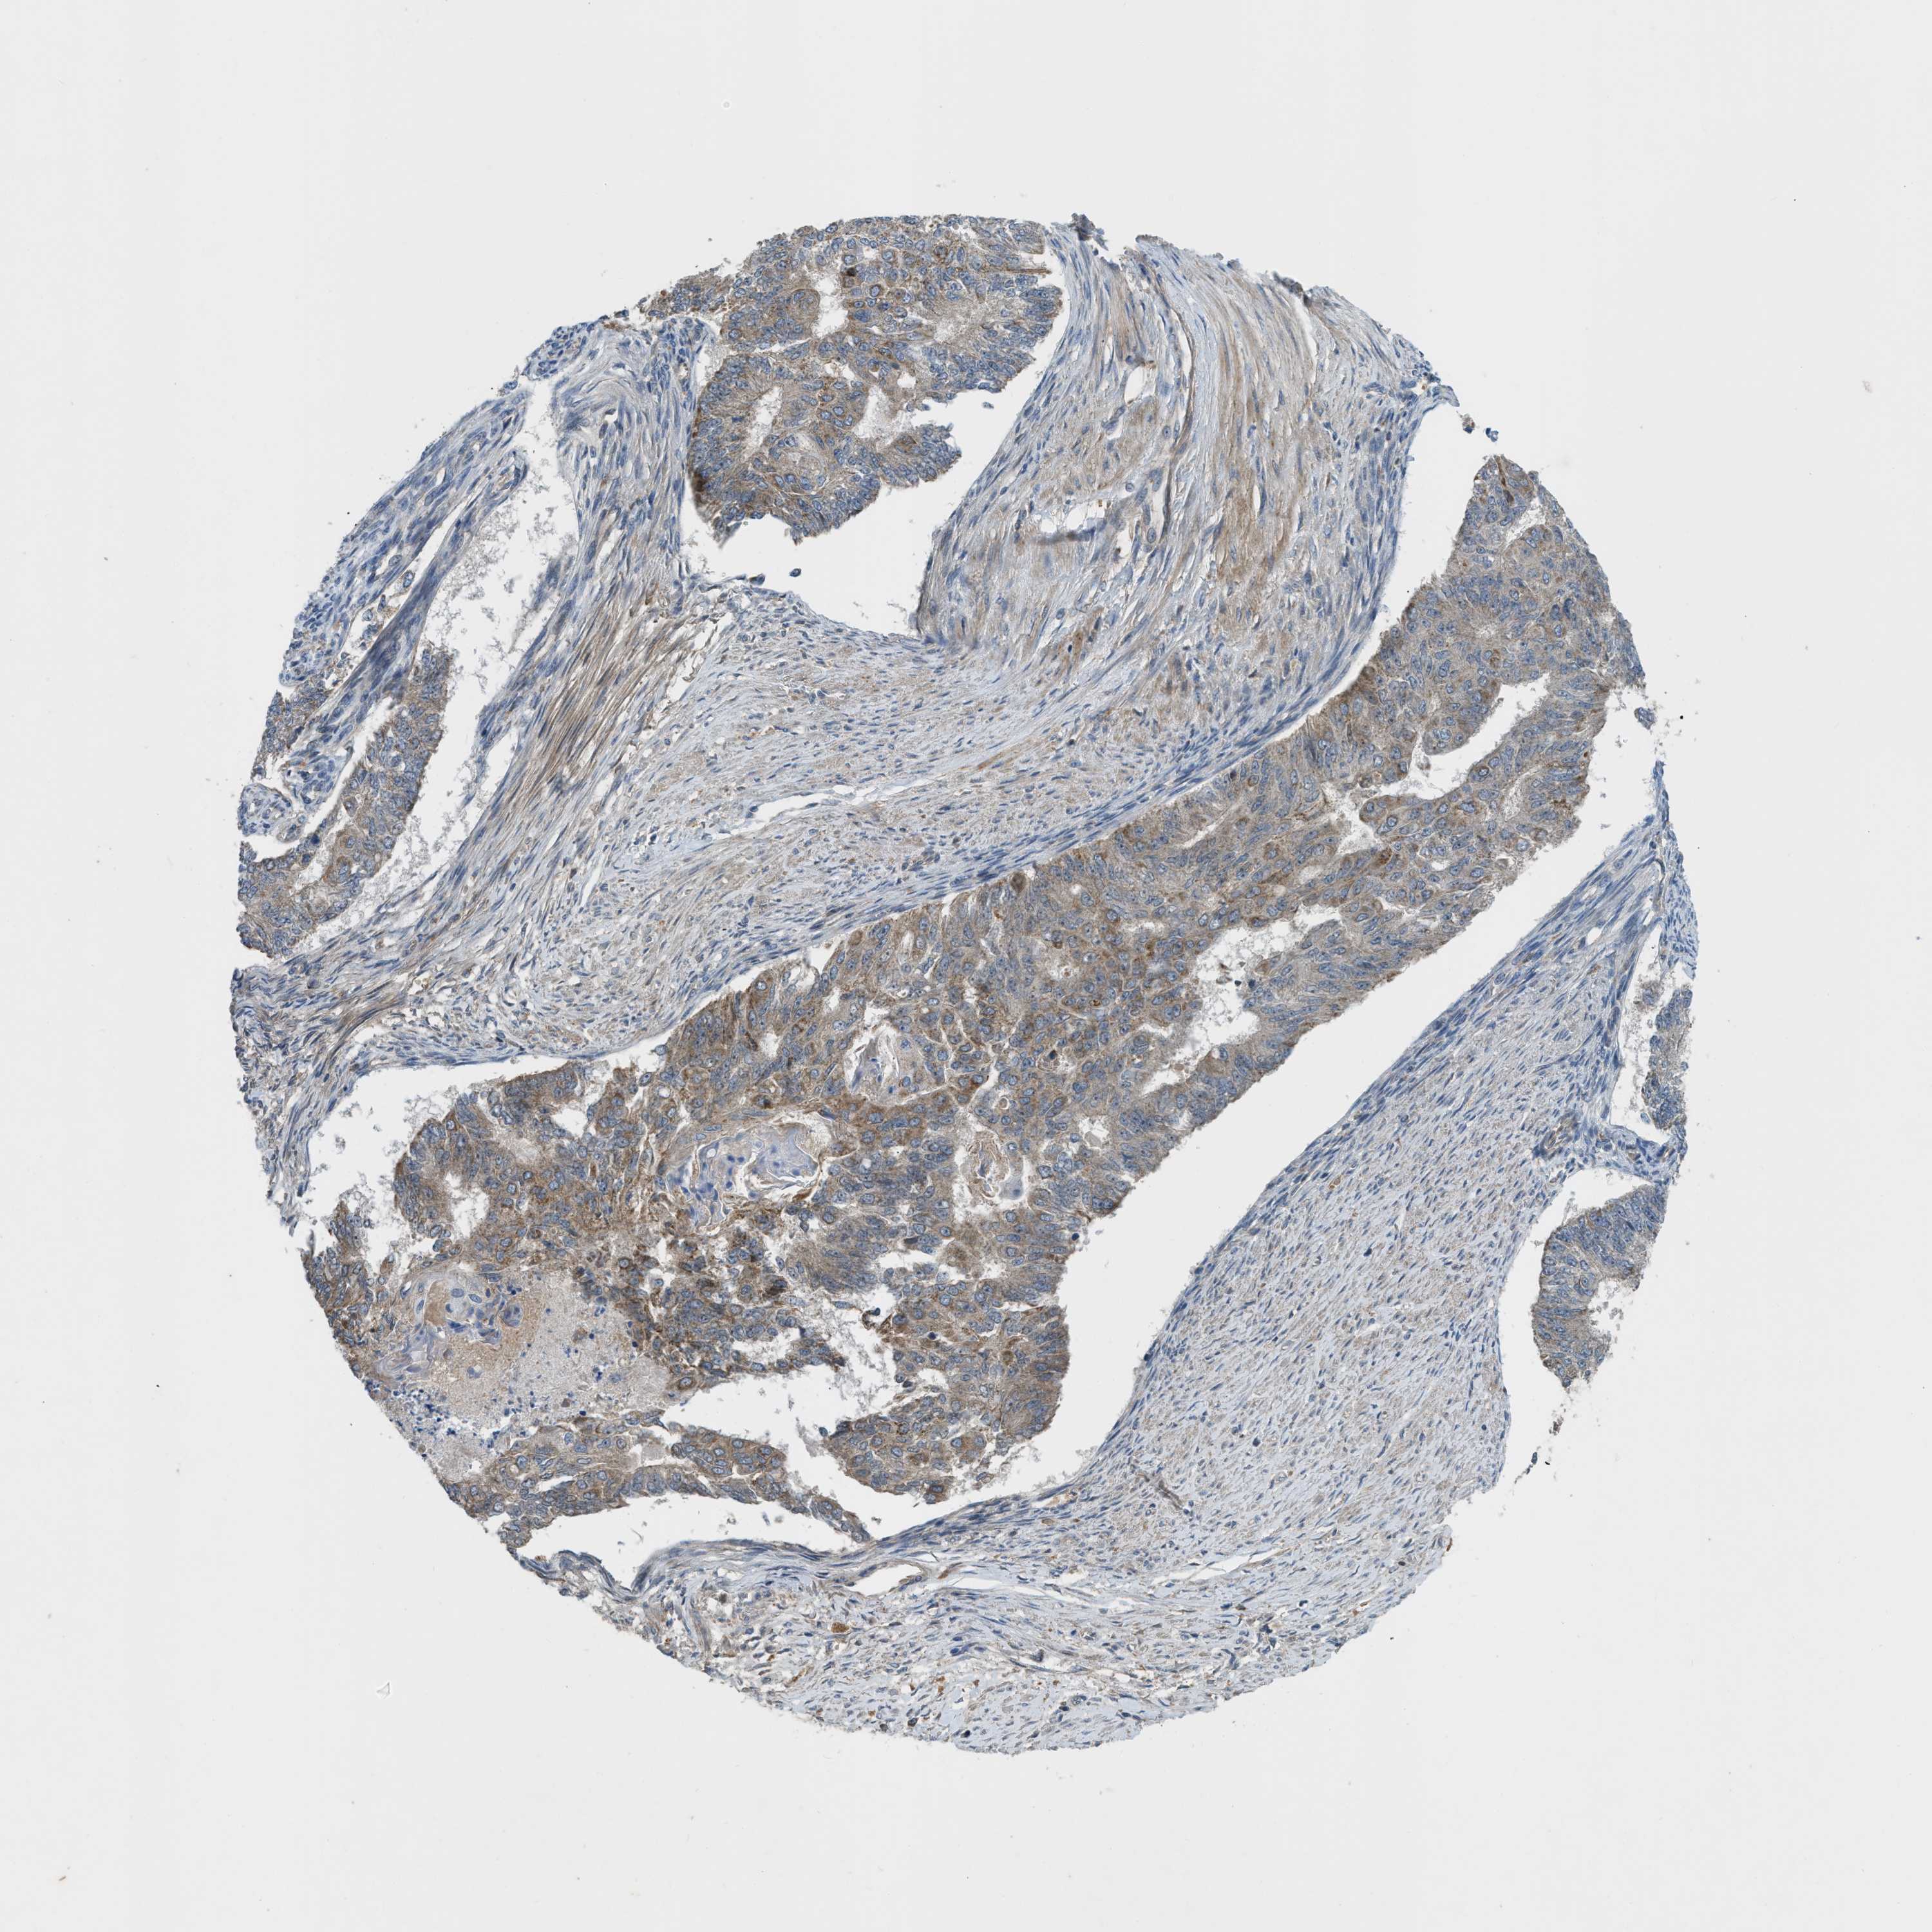

ENDOMETRIAL CANCER - Protein expressioni

A mouse-over function shows sample information and annotation data. Click on an image to view it in a full screen mode. Samples can be filtered based on level of antibody staining by selecting one or several of the following categories: high, medium, low and not detected. The assay and annotation is described here.

Note that samples used for immunohistochemistry by the Human Protein Atlas do not correspond to samples in the TCGA dataset.

Antibody stainingi

Antibody staining in the annotated cell types in the current human tissue is reported as not detected, low, medium, or high, based on conventional immunohistochemistry profiling in selected tissues. This score is based on the combination of the staining intensity and fraction of stained cells.

Each image is clickable and will lead to virtual microscopy that enables deeper exploration of all samples and also displays staining intensity scores, fraction scores and subcellular localization as well as patient and tissue information for each sample.

Antibody HPA018124

Staining

High

Medium

Low

Not detected

Intensity

Strong

Moderate

Weak

Negative

Quantity

>75%

75%-25%

<25%

None

Location

Nuclear

Cytoplasmic/membranous

Cytoplasmic/membranous,nuclear

Adenocarcinoma, NOS

Adenoma, NOS